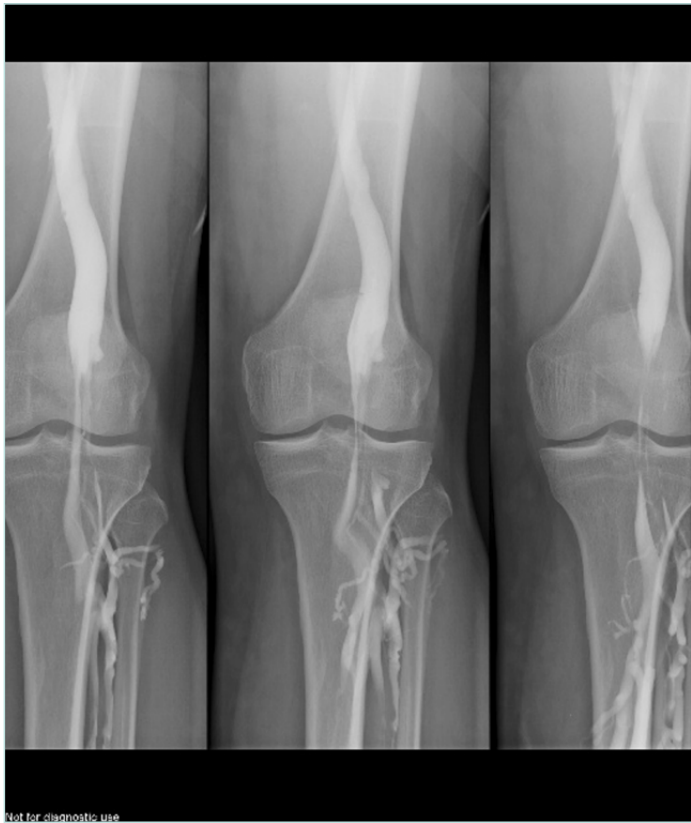

Different anatomical variations may be involved. A first condition is compression by an aberrant insertion of the lateral head of gastrocnemius; this is the most frequent situation, often associated with fibrous bands and/or fibrotic perivascular tissue; but also, a more lateral insertion of the medial head of gastrocnemius muscle to the femoral condyle can compress the vein. Another etiology is hypertrophy of the upper part in gastrocnemius and soleus muscles, with shortening of the sural triceps: type 6 in the Whelan and Rich classification.7 Obese people often present with this pattern. Figure 1 illustrates the anatomy of popliteal fossa and the classification of popliteal entrapment syndrome (into 4 types), showing common variants responsible for arterial entrapment8 A new classification into 6 types (by Levien) added type V where both popliteal artery and vein are compressed and type VI, functional entrapment: no visible anatomical anomaly, but symptoms appear during exercise due to muscle hypertrophy.9

Figure 1. Illustration of the anatomy of popliteal fossa and the classification of popliteal entrapment syndrome. Graphic illustrations show normal anatomy of popliteal fossa and common variants responsible for arterial entrapment. A) Normal popliteal artery is adjacent to and lateral to medial head of gastrocnemius muscle, which is normally attached just superior to medial femoral condyle. B) Type I. Popliteal artery takes abnormal course medial to normally attached medial head of

gastrocnemius muscle. C) Type II. Abnormal embryologic development results in medial head of gastrocnemius attached more laterally than is normal. D) Type III. Popliteal artery and gastrocnemius are normally positioned, but fibrous band is responsible for entrapment. E) Type IV. Popliteal artery courses beneath popliteus muscle. Reproduced from reference 8: Bradshaw et al. Cardiovasc Diagn Ther. 2021;11(5):1159-1167. doi:10.21037/cdt-20-186. Copyright 2021,

Cardiovascular Diagnosis and Therapy. Material under Creative Commons License CC BY-NC-ND 4.0. [The figure in reference 8 is an adaptation from Macedo TA, Johnson CM, Hallett JW, et al. Popliteal artery entrapment syndrome: role of imaging in the diagnosis. Am J Roentgenol.

2003;181:1259-1265 by permission from the Mayo Foundation for Medical Education and Research, all rights reserved.]